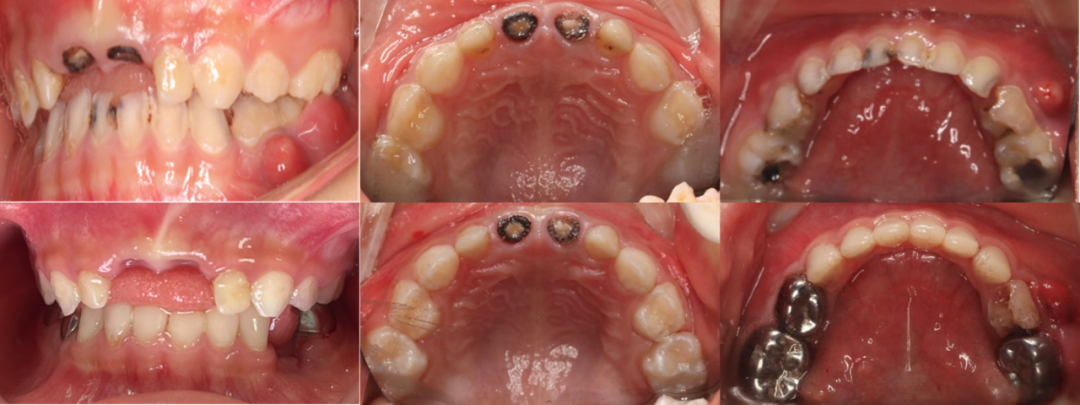

病例二:4岁的患儿从乳牙萌出就开始烂牙,来我科就诊时大牙旁边长“脓包”已经2个星期了,20颗乳牙“无一幸免“均有不同程度的龋坏,严重影响进食及睡眠。当小朋友进入诊室听到牙科高速手机的声音后,诱发了他剧烈的应激反应,变得异常哭闹抗拒,尝试数次都无法配合常规治疗。

两名患儿均存在多颗乳牙龋坏、牙髓感染甚至残根残冠的问题,因年龄小、配合度低,传统门诊治疗难以完成。口腔科多学科联合治疗小组针对不同的情况为每位患儿制定个性化、系统化的全程诊疗方案。病例一由刘钦捷主治医生、谭晓颖医师和黄芬主管护师全程在橡皮障下2小时就完成了全口口腔问题的处理,包括龋齿充填术、活髓切断术、金属预成冠修复术、滞留乳牙拔除术、即刻固定嵌入式间隙保持器的制备及全口涂氟等。病例二由谭晓颖医师和林慧芬主管护师完成,包括一次性根管治疗、前牙美学微创树脂冠修复、金属预成冠修复、窝沟封闭、残根残冠拔除等治疗。这些在门诊需要孩子与家长请假复诊多次的治疗操作,如今只需2至3小时即可完成。

▲病例二